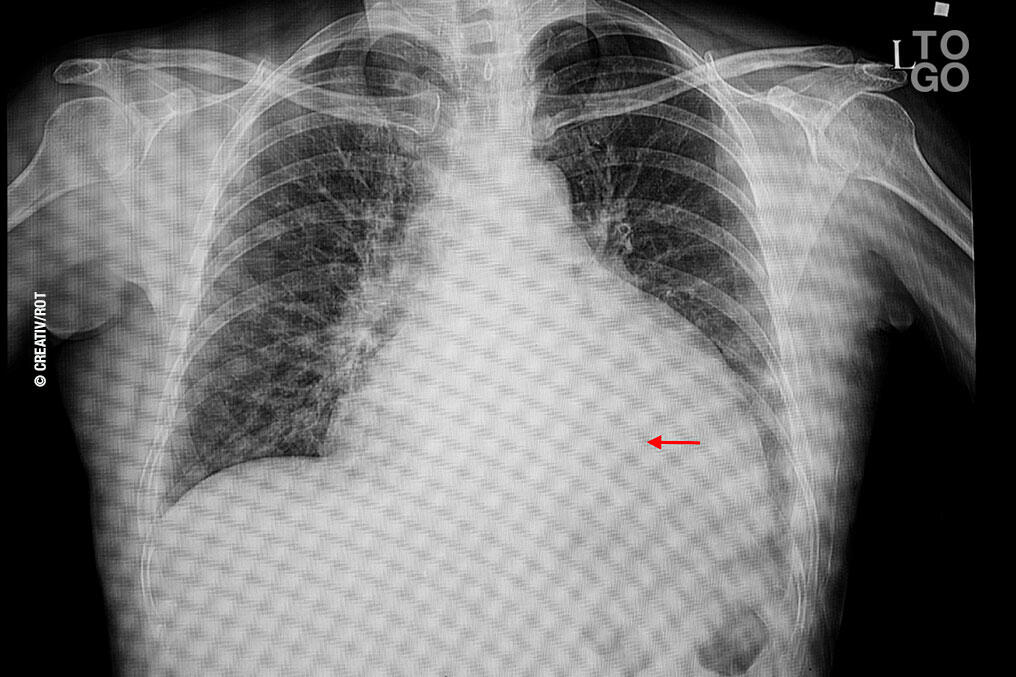

Un film de rayons X sur la poitrine d'un patient avec une cardiomégalie

L'hypertrophie du cœur touche de plus en plus de togolais.

Aussi appelée cardiomégalie, il s’agit d’un accroissement de la taille du cœur.